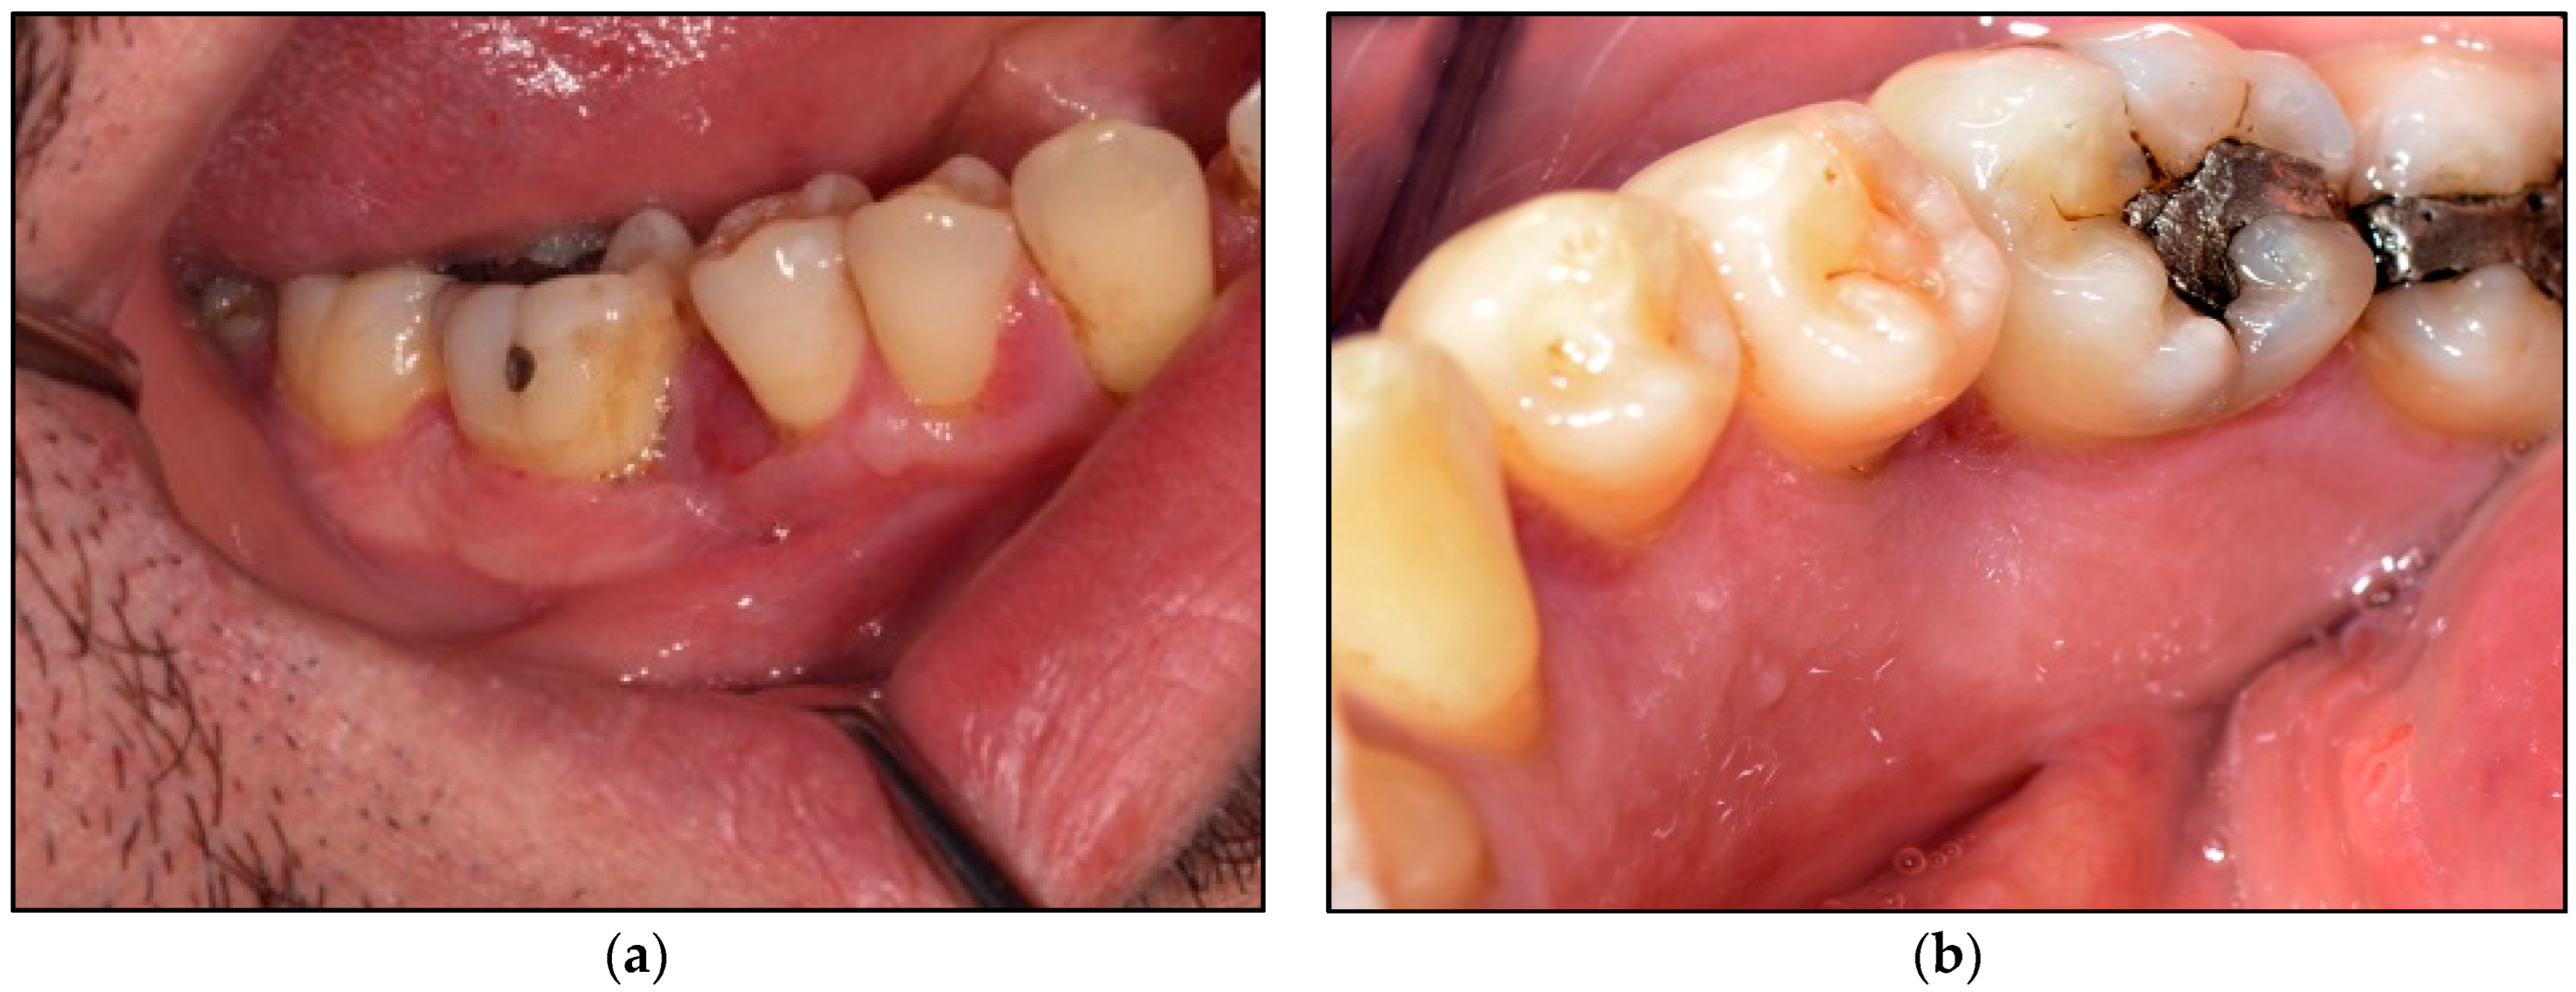

Extraoral examination revealed no pathological abnormalities including no facial asymmetry or no lymphadenopathy. Whereas, intraoral examination revealed an exophytic granulomatous lesion associated with the buccal marginal gingivae of the LR5 and LR6, invading the interdental papillae to loop lingually and extended to involve the lingual marginal gingivae of the above-mentioned teeth. The lesion was an erythromatous, sessile or pedunculated nodule with an irregular texture that was elastic moderate in consistency, an isolated lump of 1 × 1 cm in diameter on the buccal aspects of LR5 and LR6 (Figure 2a) and 1 × 1 × 1.5 cm in diameter on the lingual surfaces fixed to the underlying structures of the above-mentioned teeth (Figure 2b). There was no sign of induration or ulceration, and it tended to bleed on probing and was pulsatile on palpation. The rest of the oral mucosal tissues were normal. All the teeth were immobile clinically and there was no evidence of any dental abnormalities.

Figure 2. Shows the clinical presentation of the oral mucosal lesions. (a) represents erythromatous, pedunculated lesion with irregular texture, moderate in consistency, about 1 × 1 cm in diameter occupying the buccal gingivae and the entire interdental region between LR5 and LR6 buccally, firmly attached to the underlining structures; (b) represents a lobulated erythromatous, spongy (moderate in consistency) lesion about 1 × 1.5 × 2 cm in size, occupying the entire interdental papillae and the lingual mucosa between LR5 and LR6, firmly attached to the underlining structures.